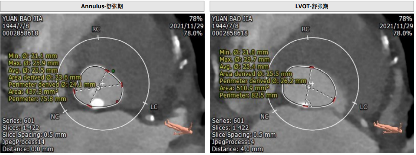

主动脉CT

该患者主动脉瓣为Type 0型二叶瓣,瓣叶中度钙化,钙化分布不均匀,主要分布左瓣,瓣环周长76.1mm,平均直径23.9mm;LVOT周长81.1mm,平均径25.0mm;钙化延伸至流出道10.5mm。左窦位置瓦氏窦瘤样膨出。瓣上6mm/8mm预估可推开空间周长70.7mm/67.5mm。左冠高度14.5mm,右冠高度18.3mm。